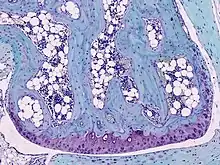

![]() Light micrograph of undecalcified hyaline cartilage showing chondrocytes and organelles, lacunae and matrix. | |

Cartilage is composed of specialized cells called chondrocytes that produce a large amount of collagenous extracellular matrix, abundant ground substance that is rich in proteoglycan and elastin fibers. Cartilage is classified in three types, elastic cartilage, hyaline cartilage and fibrocartilage, which differ in relative amounts of collagen and proteoglycan.